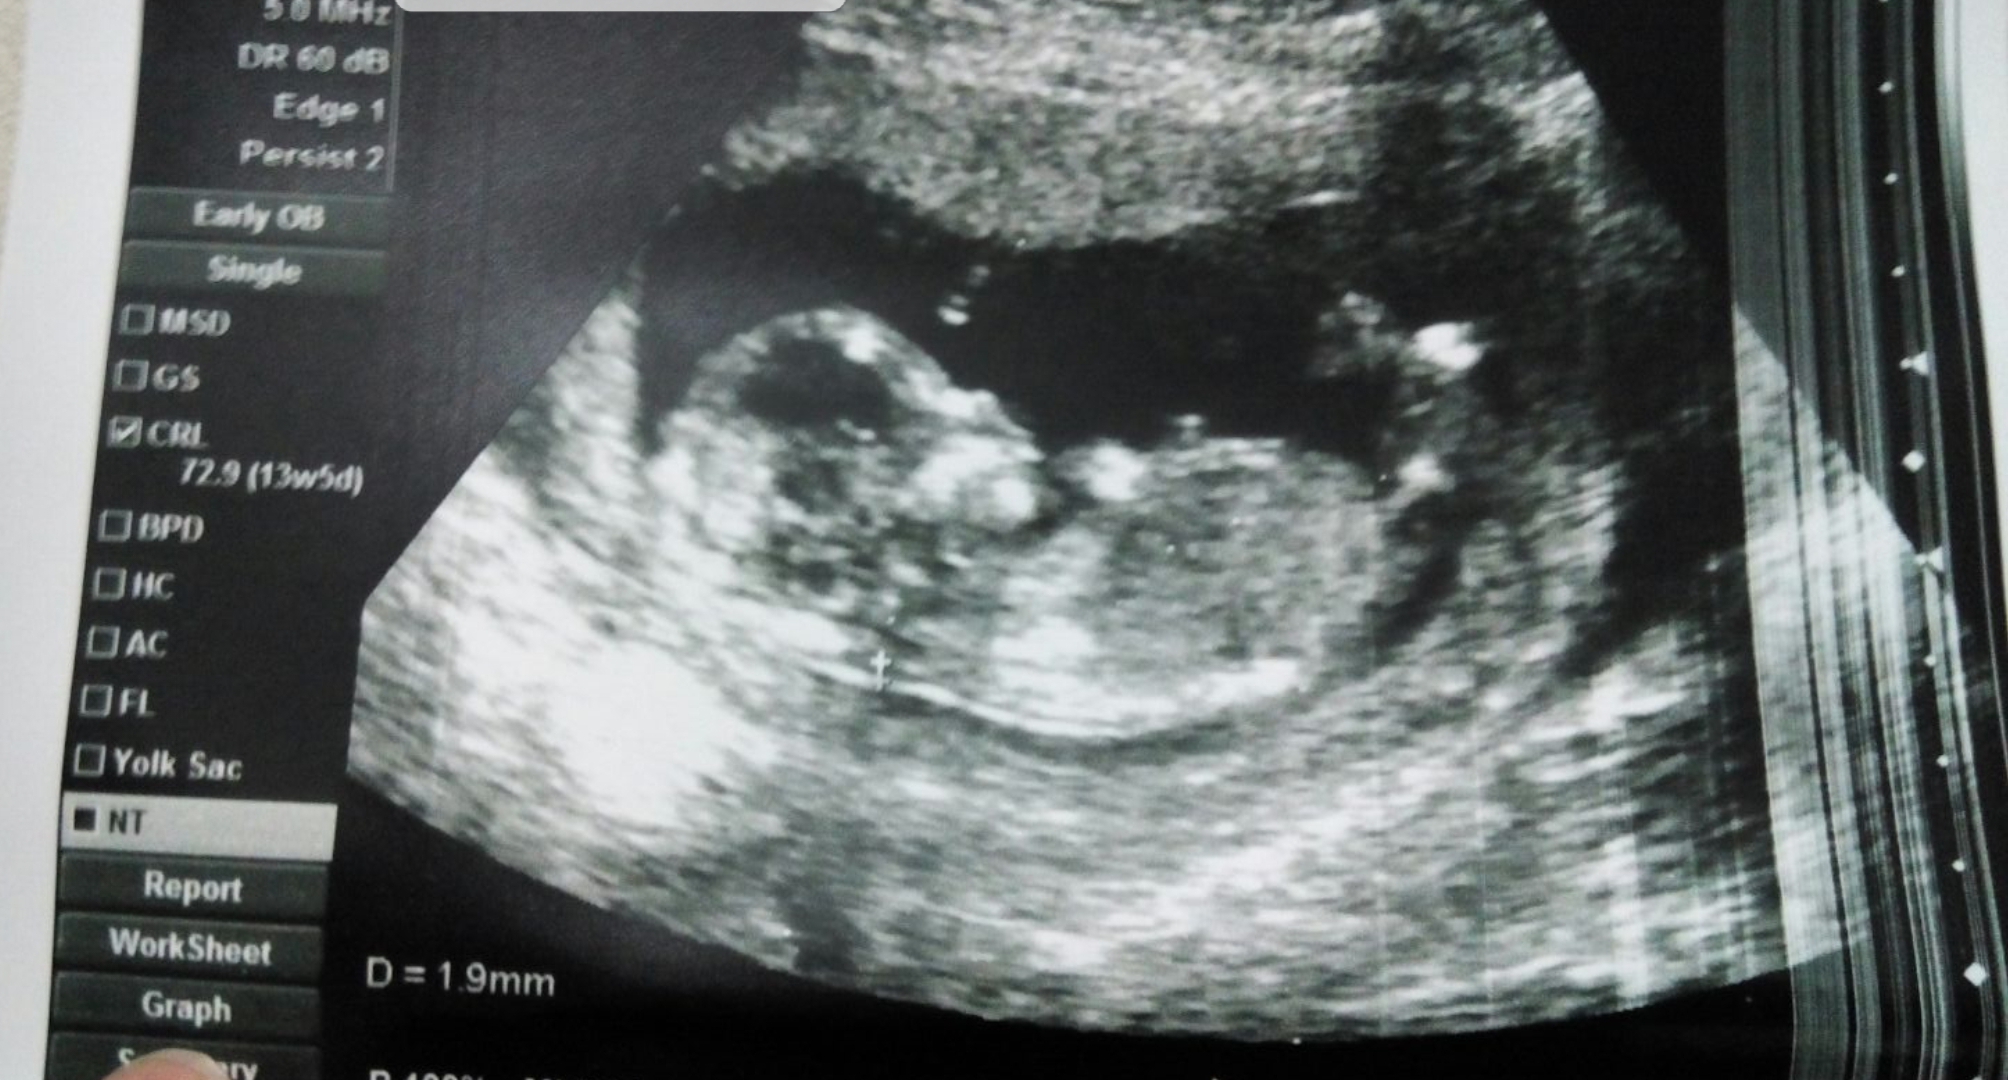

merhaba fotograflara gore bebegimin cinsiyetini yorumlar misiniz

Merhaba, ultrason görüntüleri ışıktan çok çabuk etkileniyor dolaysıyla çözünürlük kayboluyor. Bir görselde bebeğin cinsiyeti erkek bir diğerinde kız görünüyor. Emin olmamakla birlikte bebeğinizin cinsiyetinin kız olduğunu düşünüyorum. 17-19 20 . haftalarda bebeğinizin cinsiyetini net olarak öğrenebilirsiniz.

Merhaba, ultrason görüntünüzün kalitesi iyi değil. Nub çıkıntısı belirsiz .Emin olmamakla birlikte bebeğinizin cinsiyetinin kız olduğu kanısındayım. Hatırlatma fayda var bebeğinizin cinsiyetini net olarak 17-19-20. haftalarda öğrenebilirsiniz.